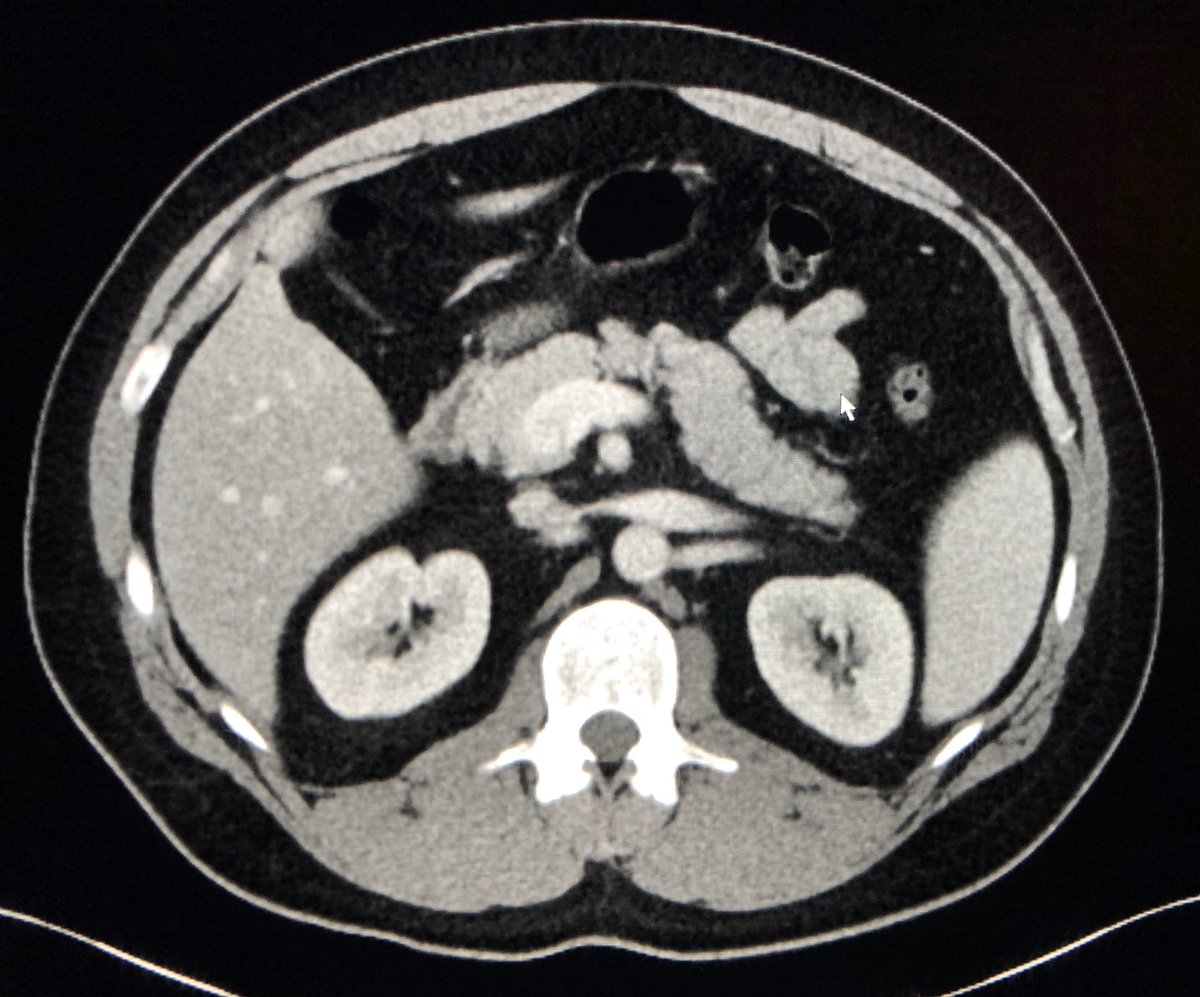

Classic! Care to guess what this appearance is pathognomic of?pic.twitter.com/11wHLxGGdr